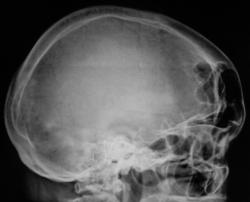

Представлены, на диске, такие изображения черепа.

Представлены, на диске, такие изображения черепа. Что посоветуете уважаемые коллеги?

Уважаемый  Валентин Львович, я так понимаю Вас смущает ячейки лобной пазухи? В данном случае надо обратить внимание на толщину костей крыши черепа, а следовательно и на турецкое седло, следует проконсультироваться у эндокринолога с дальнейшим проведением МР-исследования гипофиза.

Кости свода толстоваты, пазухи крупные. Турецкое седло не изменено. По-моему, стоит беспокоиться, только если есть эндокринные нарушения.